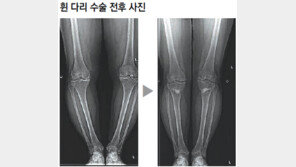

《직장인 신모 씨(53). 걷거나 오래 서 있으면 왼쪽 무릎이 욱신거린다. 특히 계단이나 경사진 길을 오르내릴 때면 힘이 무척 든다. 신 씨는 무릎 치료를 위해 동네 병원부터 대학병원까지 다니며 다각도로 치료법을 찾았다. 하지만 대부분 진통제를 처방하거나 수술을 권유했다. 그러…